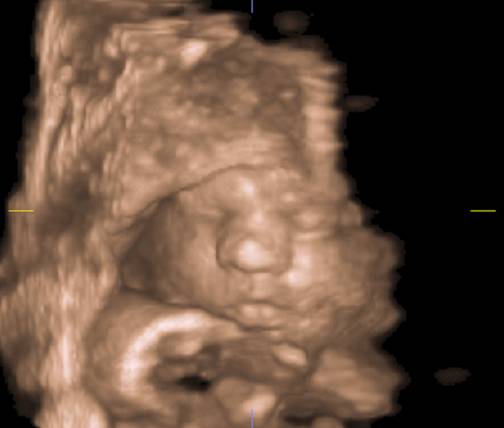

Fig. nr. 167. Fata fetala la ecografia 3D/4D

Fig. nr. 168. Plan de sectiune oblic coronal, derivat din planul XIV, ce pune in evidenta maxilarul osificat la 16 sapt.